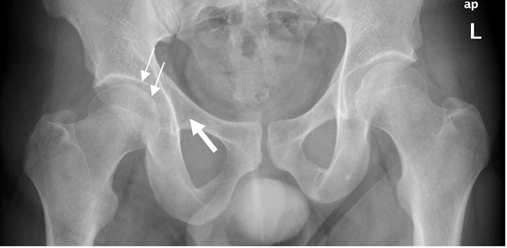

Fig 56. Fractura de acetábulo.

Rx AP. En el lado derecho hay fracturas oblicuas sobre el acetábulo (Flechas delgadas) y en el ramo iliopúbico. (Flecha gruesa). En la cadera izquierda no se aprecian alteraciones.